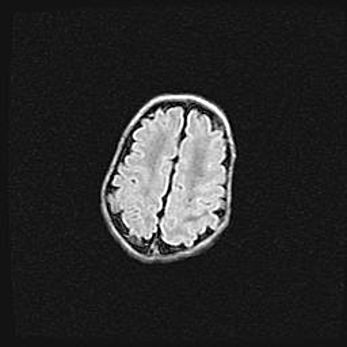

Наружная гидроцефалия с возможной атрофией височных областей.

Возраст: 28 дней

Вес: 3670 г

Пол: мужской

Окружность головы: 38 см

Срок гестации: 40 недель

Гидроцефалия головного мозга у новорожденных – это заболевание, которое характеризуется скоплением избыточного количества спинномозговой жидкости в желудочковой системе головного мозга в результате затруднения её перемещения от места выработки к месту поглощения в кровеносную систему или вследствие нарушения абсорбции. При открытой наружной форме гидроцефалии у новорожденных расширяются и переполняются субарахноидные пространства.

При нормотензивных  формах,  которые,  как  правило,  являются  следствием  перенесенных ишемических  повреждений  паренхимы  мозга,  возможно  сочетание микроцефалии  с нормотензивной гидроцефалией. В основе данных изменений лежит атрофия больших полушарий с преимущественной  локализацией  в  лобно-височных  областях.